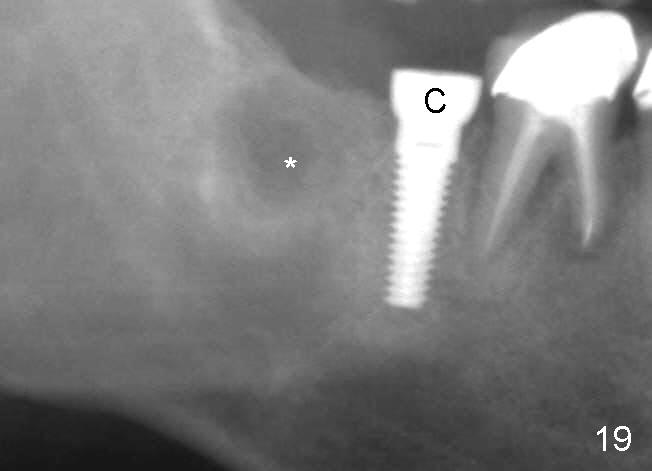

Four months postop, there is a sign of osteointegration (Fig.16 <). Graft particles migrate to the surface of the mucosa (Fig.17 <). A healing cuff is placed over the implant for preparation of restoration (Fig.18 H); graft particles are removed (<). Due to insurance issue, the restoration is yet to finish by 6 months postop (Fig.19 C: healing cuff); the cystic lesion appears to have been decreased concentrically (*). The bone density in the former cyst area continues to increase 14 and 32 months postop (Fig.20 A: abutment; Fig.22). Small piece of bone graft (<) is being extruded distobuccal to the #31 crown (C) asymptomatically 15 and 32 months postop (Fig.21,22).